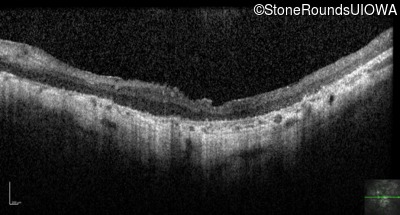

Optical Coherence Tomography - Right - Hand Motion sc

Exemplar / OCT Stack